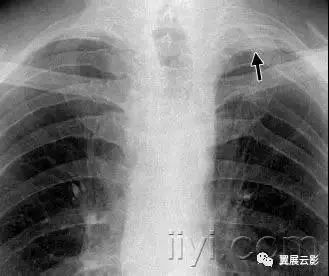

病理:不明原因的弥漫型肺泡病变。急性期特征为水肿和透明膜形成,晚期表现为含气腔隙和/或间质的机化。

病理上难以与急性呼吸窘迫综合征鉴别。平片和CT:急性期显示为双侧片状磨玻璃影,一些小叶可以不受累,产生地图样影像。在机化期,可以有结构的扭曲,牵拉性支扩,网状密度增高影。